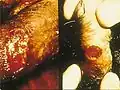

- Lésions du pénis

De petits nodules, indolores apparaissent environ 10 à 40 jours après le contact avec la bactérie. Plus tard, les nodules éclatent, aboutissant à la création des lésions tissulaires ouvertes et suintantes. L'infection se propage, mutilant les tissus infectés. En l’absence de traitement l'infection continue à détruire les tissus. Les lésions apparaissent dans les régions de contact sexuel généralement sur le pénis, les lèvres vulvaires, ou l’anus. Plus rarement, la paroi du vagin ou du col de l'utérus peuvent être le siège de lésions. Un cas dont l'évolution a nécessité l'amputation partielle du pénis a été décrit chez un patient indien infecté par le VIH-2 [9].